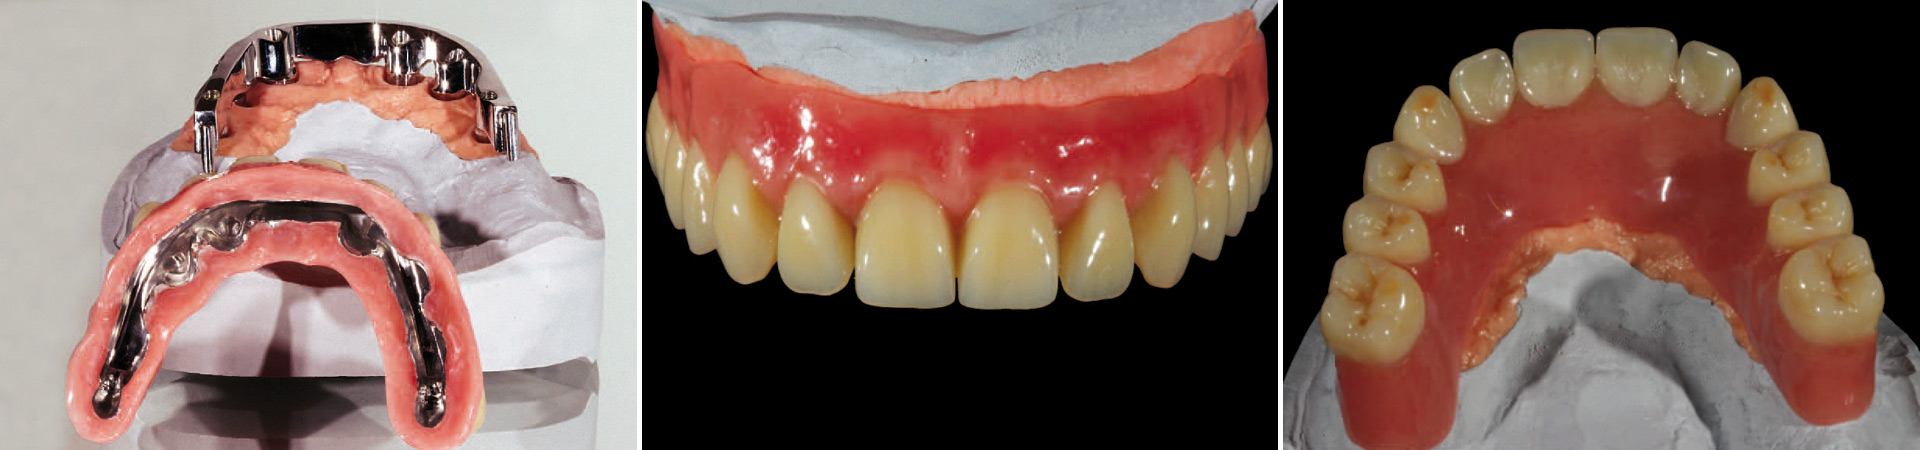

Die Stegprothese / Die fest verschraubte Brücke

Die Stegprothese

Sicherer Halt ist garantiert. Diese herausnehmbare Prothese sitzt sicher auf dem passgenauen Steg. Die Zähne werden natürlich gestaltet und mit zahnfleischfarbenen Anteilen unsichtbar im Mund fixiert. Feste Zähne, die zum Reinigen problemlos entnommen werden können. Schön und unauffällig, von eigenen kaum zu unterscheiden.